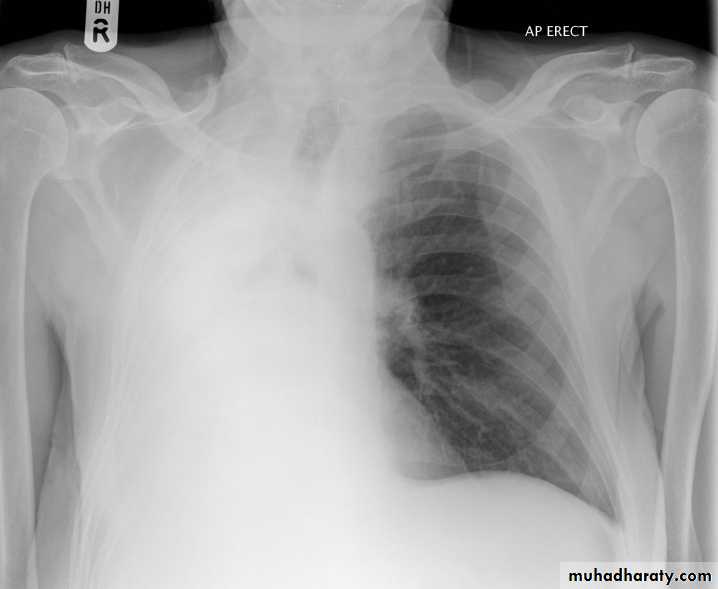

48.opasified hemi thorax Total collapse

Homogenus opacity of the right hemithorax with shifting of the trachea to the same side48.opasified hemi thorax Total consolidation

Homogenus opacity of the left hemithorax with shifting of the trachea to the same sidePleural effusion

Homogenus opacity of right lower zone with meniscus signOblitration of right cardiophrenic and costophrenic angles

Homogenus opacity of the right hemithorax

Oblitration of cardiophrenic and costophrenic angles

Shifting of the trachea to the opposite side